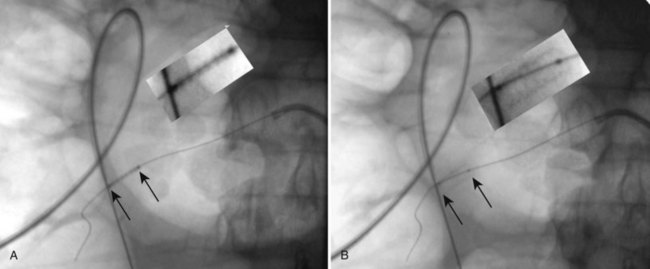

To use the “triangulation” technique, inspect the kidney with the fluoroscopy unit directly above the patient to select the desired calyx and hold the needle in the approximate position of the desired angle of entry. Rotate the top of the fluoroscopy unit cephalad and lateral, and widen the field of view with the collimator such that medial-lateral (left-right) movements of the needle are apparent. Move the shaft of the needle while keeping its tip in place until the needle is aimed toward the desired calyx (Fig. 47–20A). Then rotate the top of the fluoroscopy unit medially 45 degrees. While keeping the medial-lateral orientation of the needle constant, move the needle in the cephalo-caudad (up-down) plane until the needle is again aimed toward the desired calyx (Fig. 47–20B). Resting the forearm on the patient’s back will help stabilize the needle in one plane while moving in the other. Move the fluoroscopy unit back and forth between these two positions until the needle remains aimed at the desired calyx on both views. Advance the needle under fluoroscopic guidance while monitoring the anterior-posterior direction (depth) of the needle tip. If the needle position in the medial-lateral and cephalo-caudad planes is maintained, the needle should enter the targeted calyx.

Figure 47–20 Triangulation fluoroscopic guidance. A, With the top of the fluoroscopy unit rotated laterally and cephalad, adjust the access needle (arrows) medial-lateral orientation of the needle. B, After rotating top of the fluoroscopy unit rotated medially, and while keeping medial-lateral orientation of the needle constant, move the needle in the cephalo-caudad plane until the needle is again aimed toward the desired calyx.

(From Miller NL, Matlaga BR, Lingeman JE. Techniques for fluoroscopic percutaneous renal access. J Urol 2007;178:15–23.)